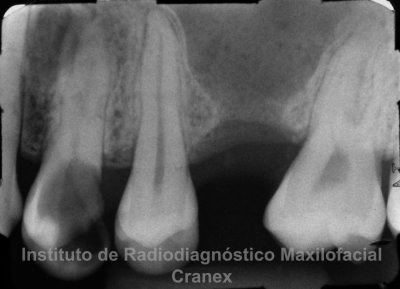

A la evaluación de las radiografías Panorámica, Waters, y radiografía Periapical, observamos, neumatización alveolar y opacificación parcial de seno maxilar izquierdo, lecho alveolar de correspondiente a pieza 2.6, con discontinuidad de la cortical de la pared basal de seno maxilar adyacente, y engrosamiento de la membrana antral de seno maxilar ipsilateral. Signos radiográficos compatibles con proceso inflamatorio sinusal (Sinusitis) en relación a comunicación buco sinusal.